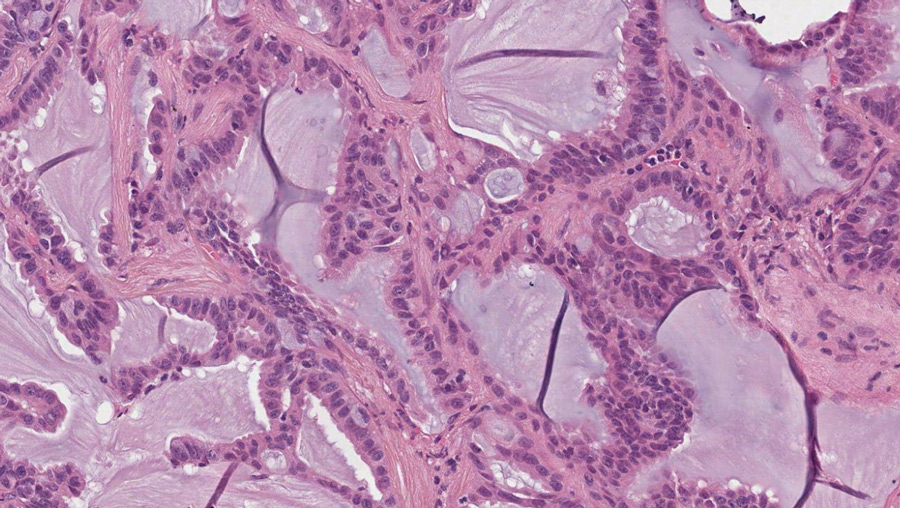

在许多类型癌症中都可以看到这种异常活性RET蛋白,其中包括神经甲状腺癌(MTC)、毛状甲状腺癌(PTC)和非小细胞肺癌(NSCLC)等实验实验证实转基因变异技术基因是这些癌症的原因,并需要异常变频活动使肿瘤细胞保活这使RET成为癌症处理的良好目标

在转移式癌症中,无法通过癌症处理完全消除的残留肿瘤会演化成抗性肿瘤,导致疾病演化辨识蛋白暴动类癌症疗法中经药改性突变对开发下一代药以抑制这些变异性至关紧要,以便把不可治愈恶性病化为可控慢性病